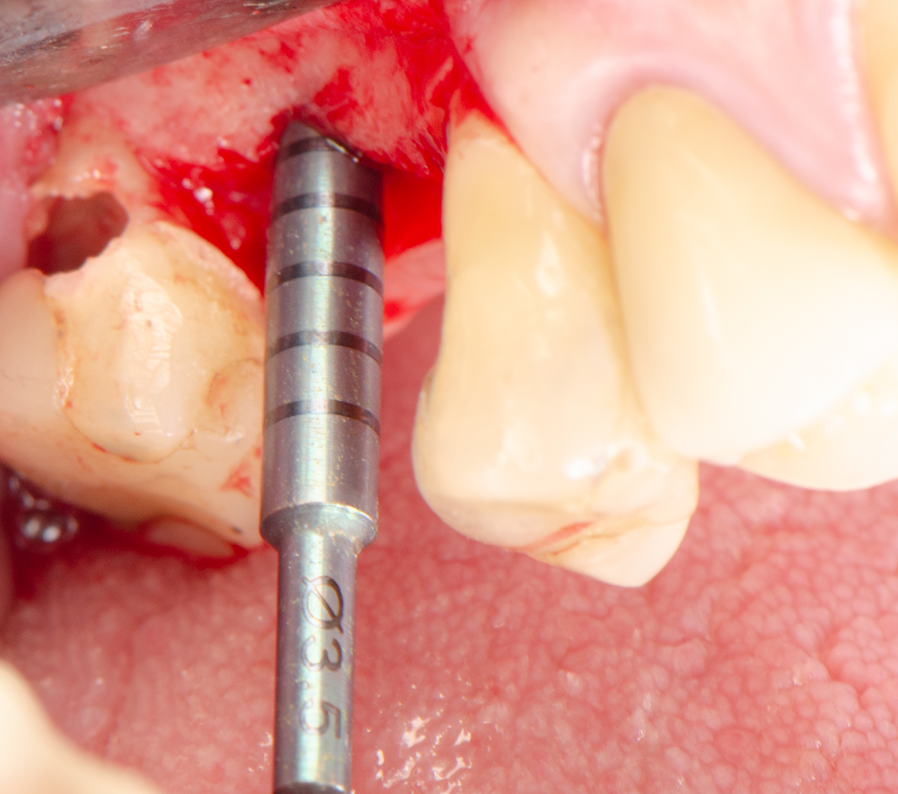

Técnica cirúrgica

Sob anestesia local, realizou-se incisão crestal na área edêntula do dente 16. O sítio foi marcado com broca lança e fresado conforme protocolo Implacil Osstem para implantes de 4,0 mm. O implante Maestro Superiore 4,0 × 9 mm foi instalado, apresentando torque progressivamente elevado até a posição final, com plataforma 2 mm infraóssea. O torquímetro registrou 50 Ncm, confirmando excelente estabilidade primária, condição favorável para carga precoce ou imediata, em linha com a literatura que destaca a alta fixação inicial dos implantes Maestro sem comprometer o osso circundante.